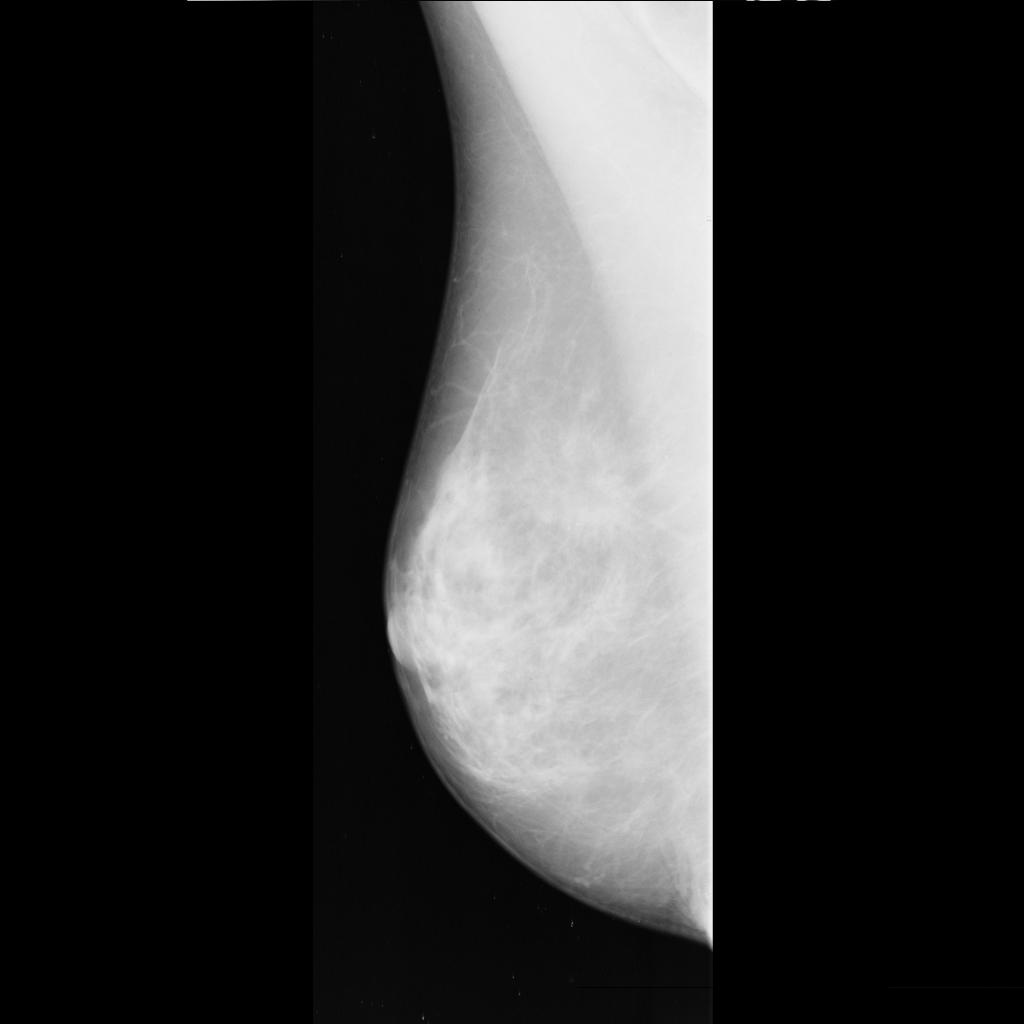

benign